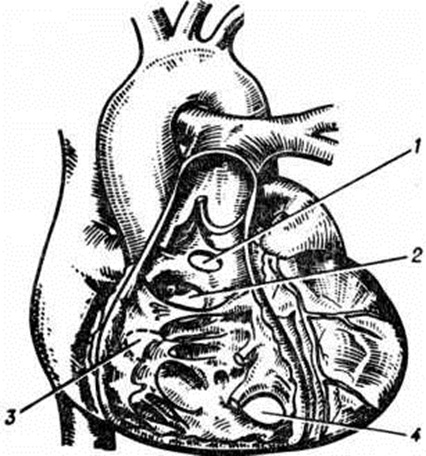

Рис. 1.

Схематические изображения отдельных врождённых пороков сердца: а — норма; б — аномалия Эбштейна — смещение трёхстворчатого клапана в сторону правого желудочка, сопровождающееся его деформацией, увеличением полости правого предсердия и уменьшением полости правого желудочка; в — аортальный стеноз; грамм — атриовентрикулярный канал (полная форма) — патологическое сообщение между предсердиями и желудочками, формирующееся в результате сочетания дефектов межпредсердной и межжелудочковой перегородок с деформацией атриовентрикулярных клапанов; д — дефект межжелудочковой перегородки; е — дефект межпредсердной перегородки; ж — коронарно-сердечный свищ — аневризматическое расширение коронарной (правой) артерии (вследствие заброса крови из полости сердца); з — прорыв аневризмы синуса Вальсальвы; и — трёхкамерное сердце с единым желудочком; к — пентада Фалло — стеноз лёгочного ствола, сочетающийся с декстропозицией аорты, дефектами межпредсердной, межжелудочковой перегородок и гипертрофией правого желудочка; л — тетрада Фалло — стеноз лёгочного ствола, сочетающийся с декстропозицией аорты, дефектом межжелудочковой перегородки и гипертрофией правого желудочка; м — триада Фалло — стеноз лёгочного ствола, дефект межпредсердной перегородки и гипертрофия правого желудочка; 1 — верхняя полая вена, 2 — правое предсердие, 3 — правый желудочек, 4 — лёгочный ствол, 5 — аорта, 6 — лёгочная вена, 7 — левое предсердие, 8 — левый желудочек, 9 — нижняя полая вена, 10 — единый желудочек; направления кровотока обозначены пунктирными стрелками, локализация пороков — сплошными стрелками.